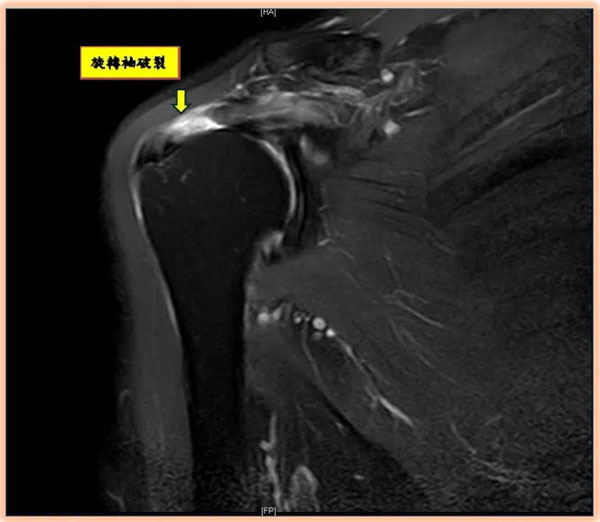

旋转肌袖破裂如何诊断?陈昱彰表示,起初常被误认为肌腱拉伤或五十肩,但症状久未改善时,应尽早请骨科医师进行正确诊断与治疗。诊断方式除理学检查、X光、超音波外,也常以核磁共振(MRI)确认破裂程度与型态,作为手术规划依据。

陈昱彰指出,若确诊旋转肌袖破裂应及早治疗。可采小切口或关节镜手术,进行肌腱缝合、清除沾黏及磨除肩峰下骨刺,依破裂型态与大小,手术可能需以医疗铆钉固定缝,现今铆钉材质包括金属、塑胶、生物可吸收及全线缝合等。自2025年下半年起,健保部分给付缝合铆钉,减轻病患负担并提供更多选择。